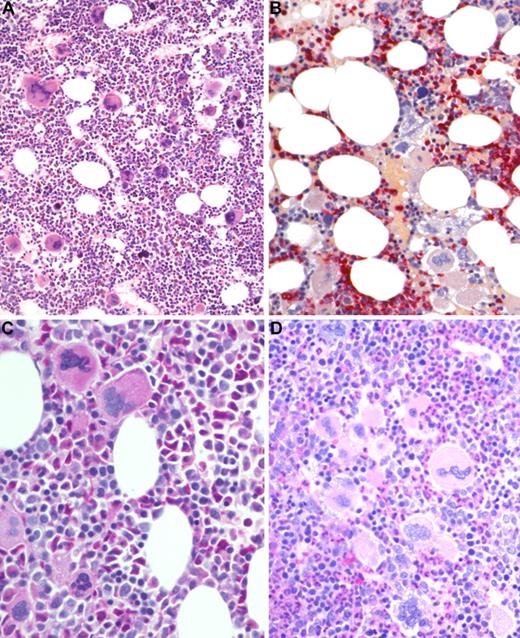

BM biopsy histology in ET/PV in low-power (×170) or medium-power (×350) field. (A) Survey with hematoxylin and eosin-stained section shows hypercellularity with conspicuous small to giant megakaryocytes and increased erythropoiesis and granulopoiesis. (B) Chloroacetate esterase reaction indicates panmyelosis or a PV-like picture: proliferation of neutrophil granulopoiesis (red) and large inlets of nucleated erythroid precursors intermingled with small to large megakaryocytes. (C) PAS staining demonstrates large to giant megakaryocytes, some with hyperlobulated (staghorn-like) nuclei surrounded by mature cytoplasms (resembling ET; see Figure 1C). (D) PAS staining with grouping of small to giant megakaryocytes with moderate nuclear lobulation consistent with a PV-like appearance. Images were acquired using Zeiss Axioplan 2, 20×/0.50 and 40×/0.60 EC PlanNeofluar.

BM biopsy histology in ET/PV in low-power (×170) or medium-power (×350) field. (A) Survey with hematoxylin and eosin-stained section shows hypercellularity with conspicuous small to giant megakaryocytes and increased erythropoiesis and granulopoiesis. (B) Chloroacetate esterase reaction indicates panmyelosis or a PV-like picture: proliferation of neutrophil granulopoiesis (red) and large inlets of nucleated erythroid precursors intermingled with small to large megakaryocytes. (C) PAS staining demonstrates large to giant megakaryocytes, some with hyperlobulated (staghorn-like) nuclei surrounded by mature cytoplasms (resembling ET; see Figure 1C). (D) PAS staining with grouping of small to giant megakaryocytes with moderate nuclear lobulation consistent with a PV-like appearance. Images were acquired using Zeiss Axioplan 2, 20×/0.50 and 40×/0.60 EC PlanNeofluar.